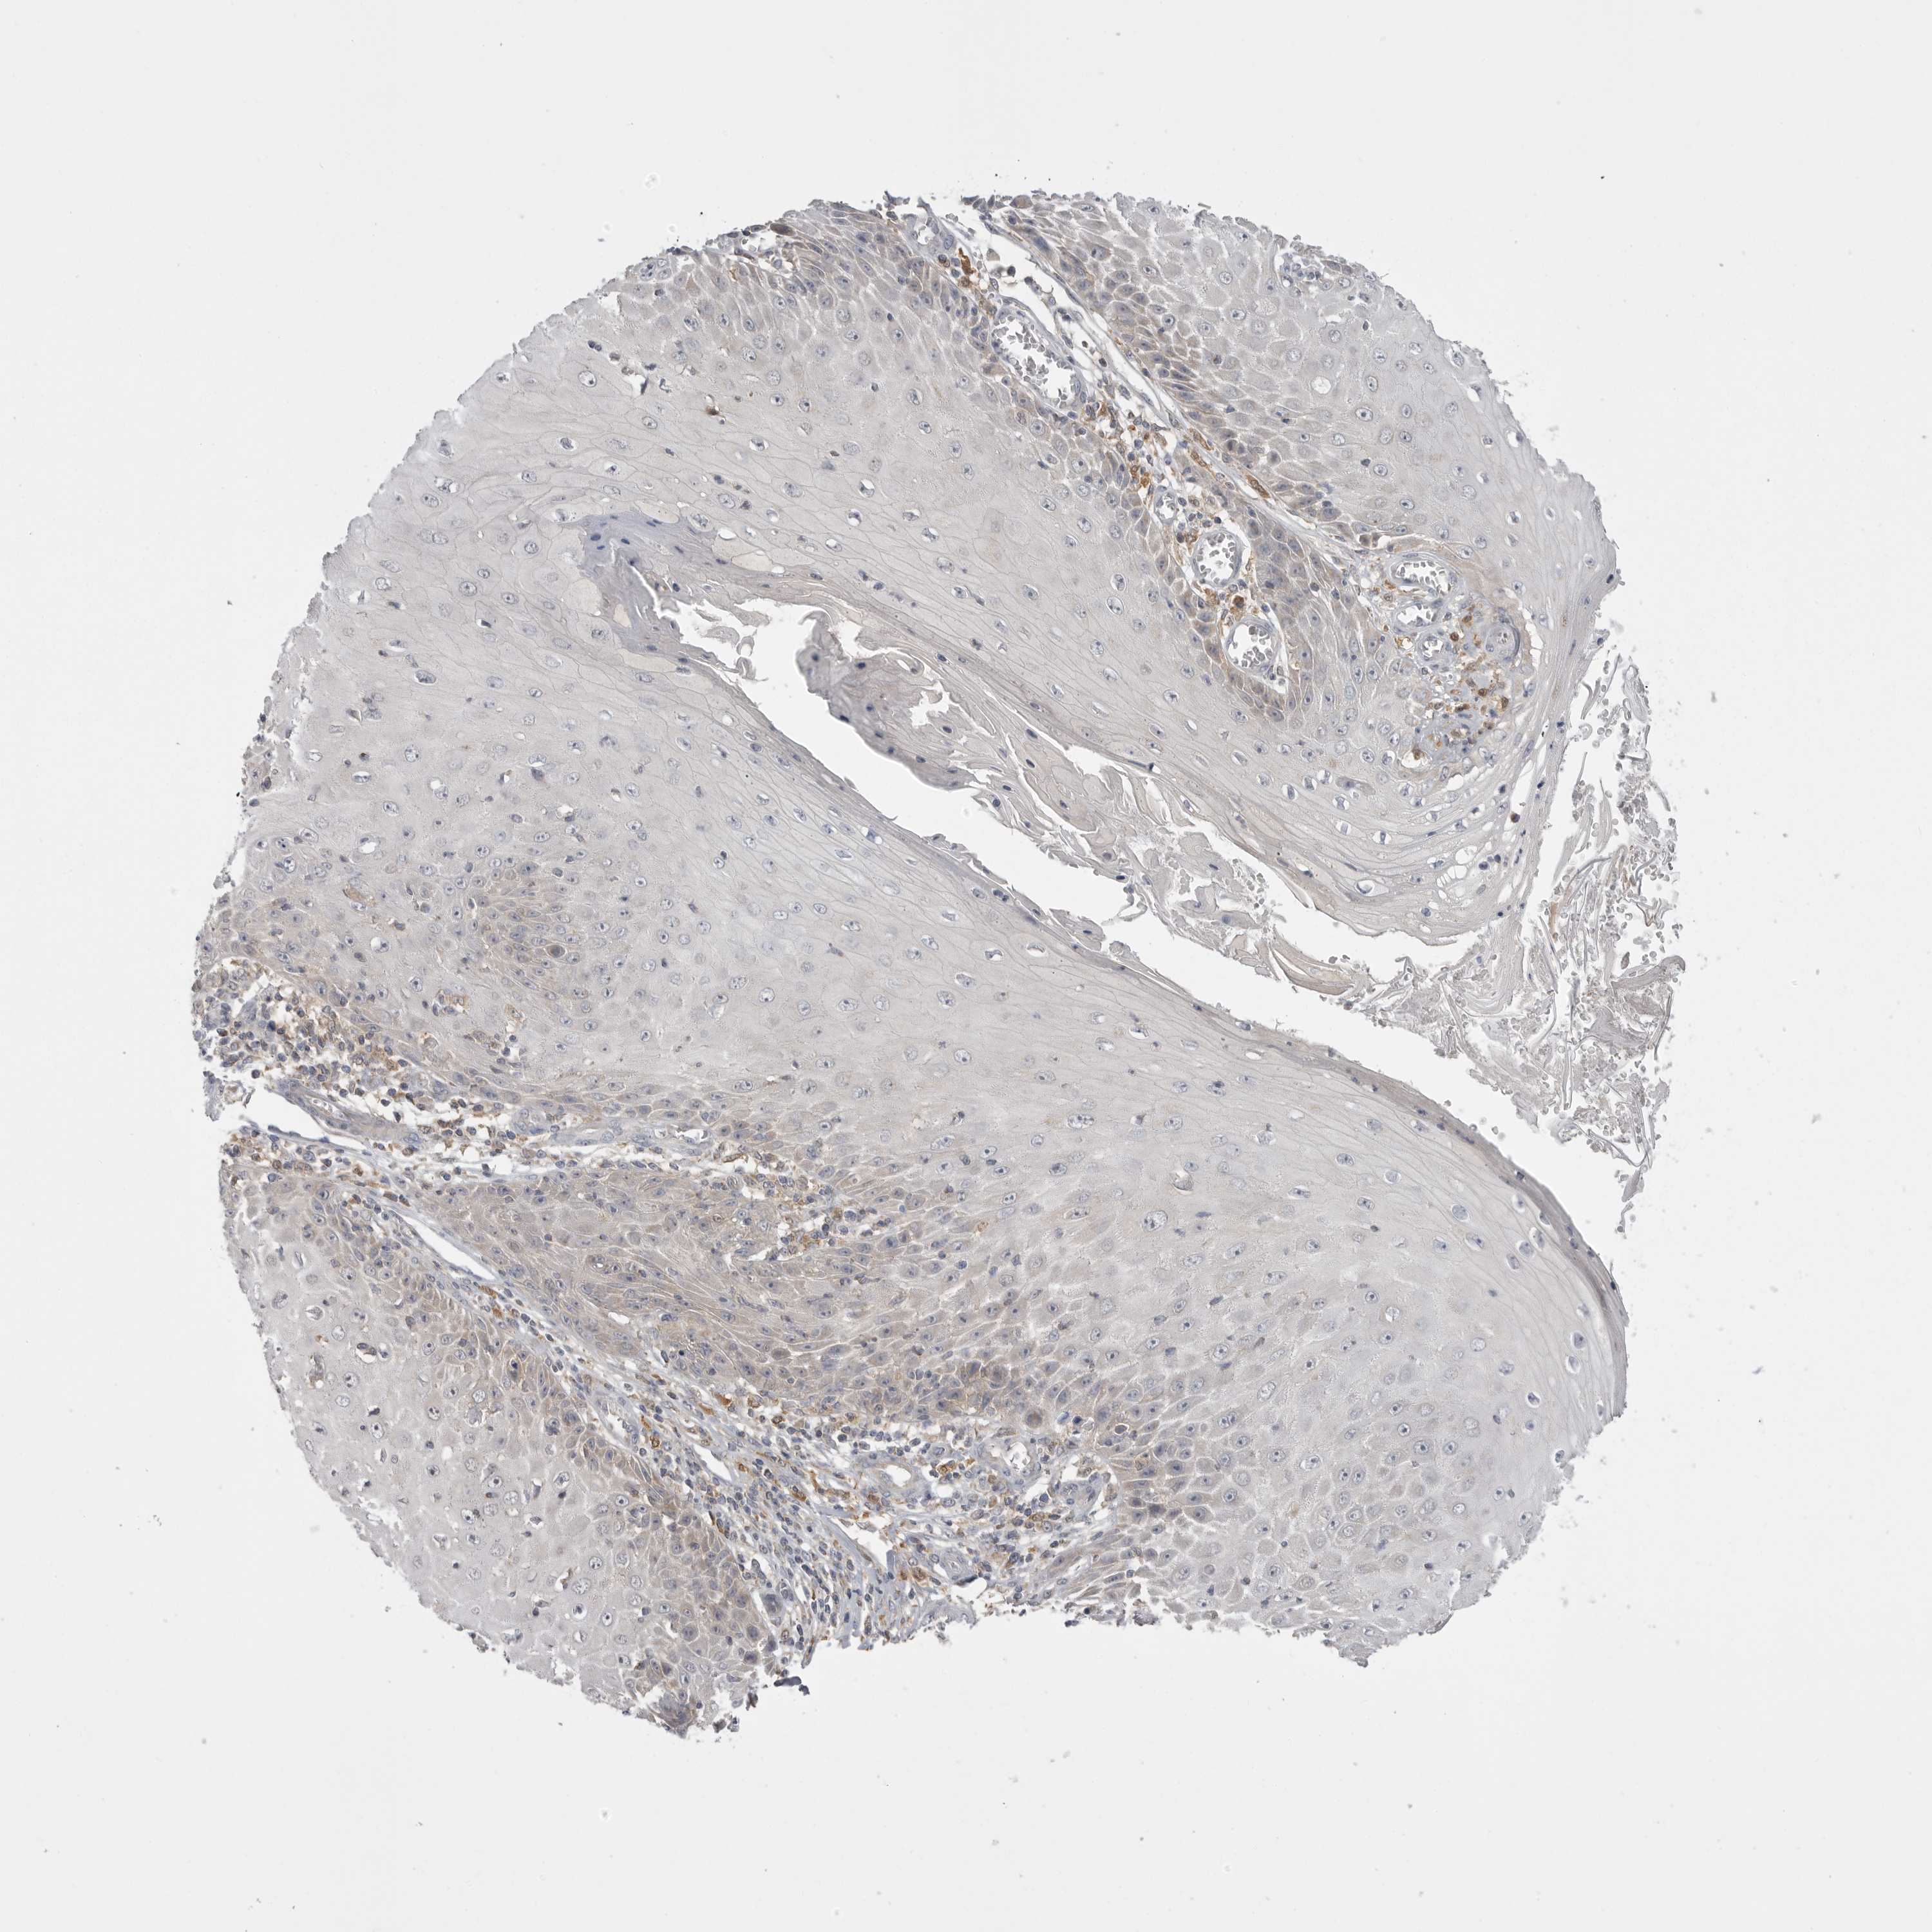

SKIN CANCER - Protein expressioni

A mouse-over function shows sample information and annotation data. Click on an image to view it in a full screen mode. Samples can be filtered based on level of antibody staining by selecting one or several of the following categories: high, medium, low and not detected. The assay and annotation is described here.

Each image is clickable and will lead to virtual microscopy that enables deeper exploration of all samples and also displays staining intensity scores, fraction scores and subcellular localization as well as patient and tissue information for each sample.

Antibody HPA027168

Squamous cell carcinoma, NOS